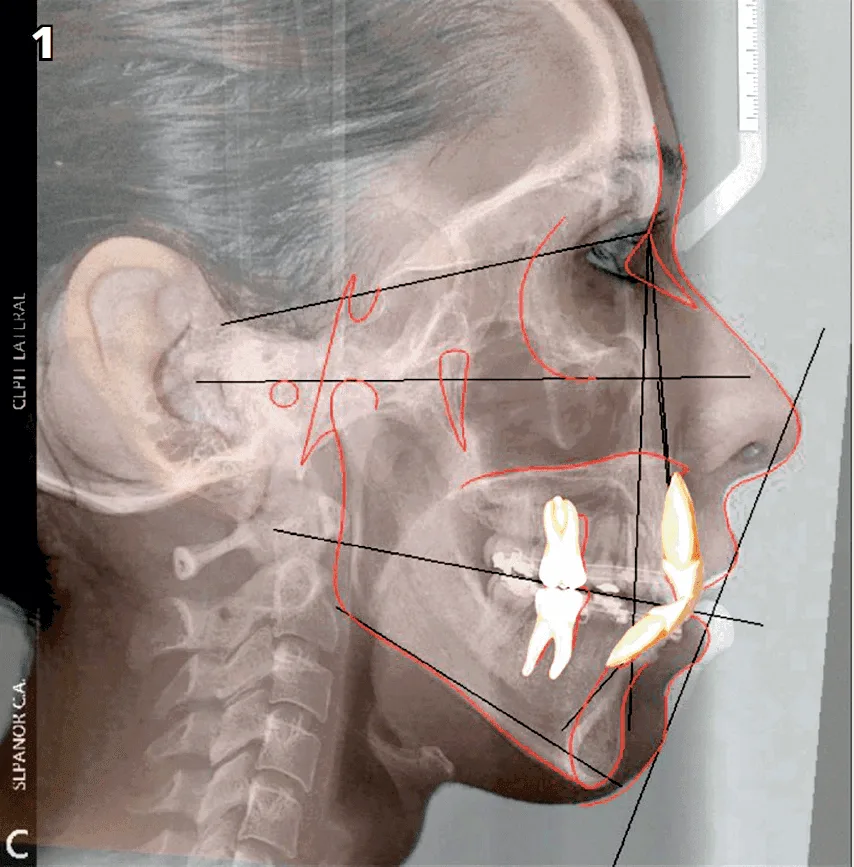

Al hacer la valoración y el examen clínico pudimos observar que se trataba de una sonrisa gingival por exceso vertical del maxilar. Corroborando estos datos con los auxiliares de diagnóstico complementario tales como: cefálica lateral, ortopantomografía, modelos de estudios y fotografías clínicas. (Fig, 1)